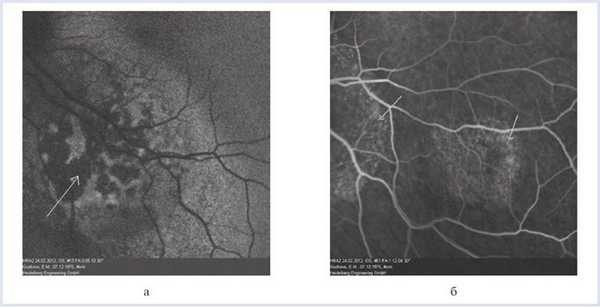

Флюоресцентная ангиография:

OS — в ранние фазы исследования определяется зона гипофлюоресценции в центральном отделе очага, в ранние венозные фазы — ангиопатия сосудов сетчатки, в средние венозные фазы — гиперфлюоресценция по периферии фокуса с формированием симптома «россыпи крупы», сохраняющегося до поздних фаз исследования.

В зоне наружного очага — симптом «россыпи крупы», сохраняющийся до поздних фаз исследования (рис. 5). Рисунок 5. Флюоресцентная ангиография метастатической карциномы хориоидеи. Гипофлюоресценция в ранние фазы исследования — белая стрелка (а); «россыпь крупы» (стрелки) юкстапапиллярного очага и малого фокуса (б).

Приведенные два клинических случая интересны тем, что оба пациента имеют онкологический анамнез и у обоих на глазном дне офтальмоскопически выявлен желтый проминирующий очаг в постэкваториальной зоне, что может указывать на метастатический характер поражения глаза. Однако при тщательном обследовании с использованием методов флюоресцентной ангиографии и спектральной оптической когерентной томографии по совокупности томографических и ангиографических симптомов в одном случае диагноз метастаза снят, а в другом подтвержден.

В первом случае гипофлюоресценция в зоне очага с гиперфлюоресценцией по его периферии в совокупности с томографически выявленной отслойкой РПЭ и сохранением ровного профиля мембраны Бруха позволяют снять диагноз вторичной злокачественной опухоли хориоидеи и установить возрастную макулярную дегенерацию.

Во втором случае гипофлюоресценция в ранние фазы исследования, симптом «россыпи крупы» в совокупности с томографически определяемым мелкобугристым изменением хориоидального профиля, наличием депозитов в слоях сетчатки, ретиношизисом дают возможность установить диагноз метастатической карциномы хориоидеи.